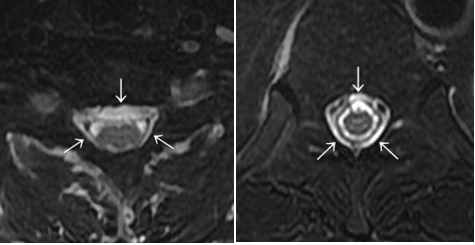

(2)DTS (Dinosaur Tail Sign:恐竜のせびれ徴候)

(「画像診断」Vol.38 No.3 2018 脳脊髄液漏出症 P325-331 )

脊髄MRI(T2強調脂肪抑制矢状断)において、硬膜嚢背側の棘間部が弓状〜棘状の高信号を呈する場合がある。本所見は、横断像のFDSS〜iFDSSを矢状断として観察しているものであり、髄液漏出を示す所見と考えられる。

鹿戸先生(山形大学教授) 選定DTS(明舞中央病院症例例)

|

その他の代表例(明舞中央病院症例より) DTS(←)とFDSS(▲)・iFDSS(⇧)↓ |